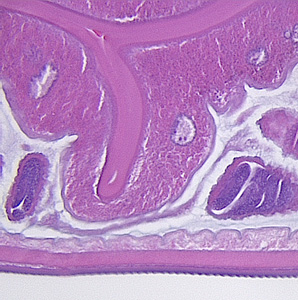

A worm-like object was removed during a routine colonoscopy performed on a 65-year-old male patient. The patient had no gastrointestinal complaints and no documented international travel. The object measured approximately 11.0 mm in length. The specimen was sent to Pathology for routine histological work-up, including sectioning and staining with hematoxylin-and-eosin (H&E). Digital images were captured and sent to the DPDx Team for diagnostic assistance. Figures A–D show four of the images sent for consultation. Follow-up ova-and-parasite (O&P) examinations of stool were negative. What is your diagnosis? Based on what criteria?

Figure A